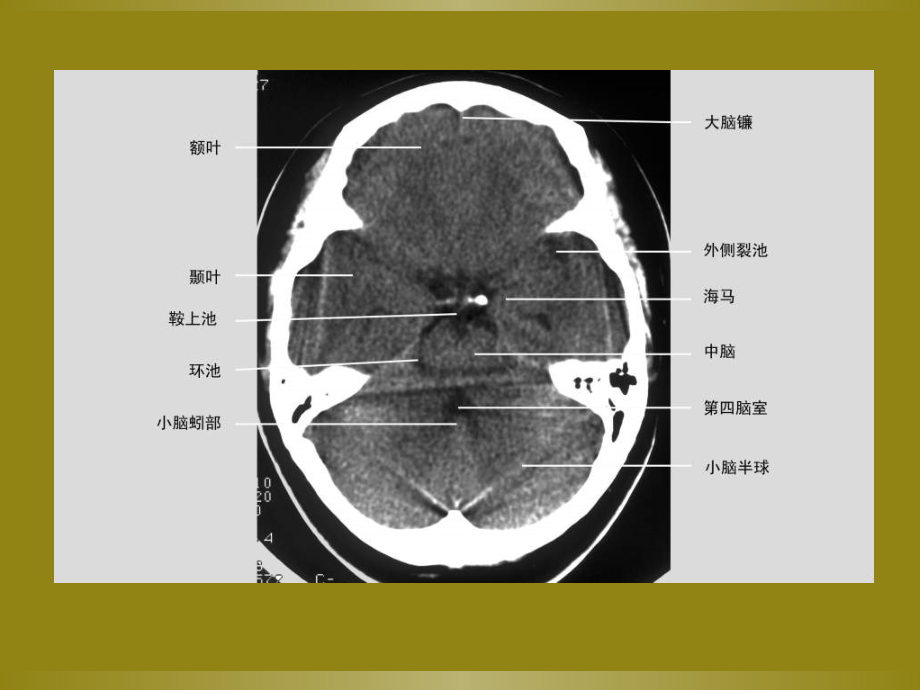

,单击此处编辑母版标题样式,单击此处编辑母版文本样式,第二级,第三级,第四级,第五级,*,*,正常颅脑,CT,表现,概论,钙化是颅脑,CT,和,MR,检查的常见征象。,CT,扫描对于颅内钙化的显示和确定明显优于,MR,检查。钙化在,CT,平扫时呈很高密度。平扫呈很高密度的其他病变还包括急性出血和胶样囊肿,测量,CT,值超过,100Hu,可以确定为钙化。颅内钙化原因很多,可以是生理性的,也可以是病理性的。,CT,值是表示该部分,X,线衰减的数据,以,hunsfiled,即,Hu,为单位。物体的密度愈高则,CT,值愈大,密度愈低则,CT,值愈小。扫描后,可以随时对扫描野内任何部分加以测定,同时在画面上显示出,CT,值数。例如水为,0,,肺组织为,-1000,,而骨组织可高达,+1000,以上。,一、生理性钙化,颅内钙化以生理性钙化最为常见,为正常表现,通常没有临床意义。认识生理性钙化是确定病理钙化的前提和基础。生理性钙化的种类很多,仅介绍常见的几种。,生理性钙化种类,1,、松果体钙化,2,、脉络膜丛钙化,3,、大脑镰钙化,4,、基底节钙化,5,、小脑齿状核钙化,6,、其他部位硬脑膜钙化,1,、松果体钙化,它是颅内钙化最常见的生理性钙化之一。约,75%,以上的正常成人表现为松果体钙化。绝大多数松果体钙化为生理性钙化,没有临床意义。,但应注意:,1,、钙化的松果体是否偏离中线,明显偏离中线时应仔细观察有无早期松果体区肿瘤,必要时,MR,检查确定;,2,、松果体钙化团块太大,直径超过,10mm,时,应怀疑松果体区肿瘤;,3,、,10,岁以下儿童出现松果体钙化时,应警惕有松果体区肿瘤存在(,图,1,)。,图,1,CT,平扫显示松果体和脉络丛生理性钙化,松果体钙化,2,、脉络膜丛钙化,常规颅脑,CT,扫描时,脉络膜丛钙化主要见于侧脑室三角区,其出现率与松果体相近,钙化呈圆形或不规则形,多数情况下,脉络膜丛钙化为双侧性,形态和大小比较对称(,图,2,)。少数情况下,脉络膜丛大小可以比较大,称为脉络膜丛球,钙化时呈球状钙化。钙化的脉络膜丛也可以双侧很不对称(,图,3,),或者仅单侧出现钙化。两侧侧脑室脉络膜丛钙化明显或很不对称时,不可认为脉络膜丛乳头状瘤。,脉络膜丛钙化一般没有临床意义,但通过观察侧脑室三角区钙化的脉络膜丛有无移位及根据移位的方向对脑内等密度占位性性病变的出现和定位很有帮助。,图,2,双侧钙化的脉络丛呈球状,图,3,脉络丛两侧钙化不对称,3,、大脑镰钙化,大脑镰钙化亦较常见,多呈沿大脑镰走行的线状,也可局部钙化较显著,呈梭形或球形(,图,4,)。少数可呈多发结节状钙化(,图,5,),图,4,大脑镰前部生理性钙化,图,5,大脑镰呈多发结节状不规则生理性钙化,4,、基底节钙化,40,岁以上正常人中,颅脑,CT,扫描时发现基底节钙化也很常见,常双侧比较对称(,图,6,),但也可不对称,以苍白球钙化最为常见,苍白球的一部分钙化或整个苍白球完全钙化,钙化也可同时见于尾状核及丘脑,若无有关临床症状多属于生理性钙化。如果基底节钙化出现在,30,岁以下时,应警惕病理性钙化,病理性基底节区钙化主要为代谢性或内分泌性疾病所致,应仔细询问有无癫痫等相关临床症状或进行有关钙磷代谢和内分泌方面的生化检查。,图,6,双侧基底节区生理性钙化,基底节区钙化,5,、小脑齿状核钙化,小脑齿状核钙化比基底节区钙化少见,其意义同基底节钙化,小脑其他基底核可为生理性或病理性(,图,7,),图,7,双侧小脑齿状核生理性钙化,6,、其他部位硬脑膜钙化,小脑幕、鞍隔、岩锥后床突韧带等均可发生钙化。,CT,扫描可成条状、线状、点状很高密度影,境界清楚。钙化明显时可压迫周围结构产生相应的临床症状。,二、病理性钙化,颅内病理性钙化可以是颅内病变的一种主要表现或伴随征象,也可以是颅内病变转归和痊愈的结果。发现颅内钙化通常比较容易,但确定钙化的病变性质,尤其是确定病理钙化的原因有时比较困难。根据钙化的形态和分布特点,在分析钙化原因时可将其分为五种情况来考虑:,1,脑实质内多发、散在、结节样钙化是颅内感染性病变钙化的特点,除感染性病变外,还应该考虑到结节性硬化。,2,脑实质内双侧片状、弥漫性钙化是代谢疾病和内分泌疾病颅内钙化的特点。诊断时还需考虑生理性钙化和家族性疾病引起的钙化。,3,条样、脑回样、铁轨样、圆点状钙化是血管样病变钙化的特点,包括,A-V,畸形,脑三叉神经血管瘤病等。,4,脑肿瘤钙化。绝大多数表现为肿瘤内部分钙化,其特点为在异常密度或信号的肿瘤背景下有各种形态、程度和范围的钙化存在。少数肿瘤可完全钙化,完全钙化主要见于脑膜瘤。,5,其他没有特点的钙化。有些病变钙化没有特点,需要结合临床病史和参考钙化周围病变的影像学表现。,1,、感染性病变,很多感染性疾病可以出现钙化或痊愈后表现为钙化。特点为脑实质内多发、散在、结节样钙化,但也可以出现其他形态的钙化。仅仅根据钙化的形态、数目、大小分布确定是哪一种颅内感染常常比较困难,但有些感染性疾病颅内是有特点的,根据钙化的特点可以确定或提示诊断。,(,1,),TORCH,综合征,TORCH,综合征(,TORCH syndrome,)实际上是病毒或原虫感染脑组织引起的脑炎。主要发生于胚胎期或分娩过程中,故又称先天性宫内感染或先天性,TORCH,感染。,TORCH,一词是几种引起脑组织感染致病源英文字头的缩写,包括弓形体原虫和其他感染因素如风疹病毒、巨细胞病毒和疱疹病毒,其中疱疹病毒是胎儿期脑炎最常见的原因。,TORCH,感染脑组织主要引起坏死性脑炎,尤其容易侵犯脑室周围白质,坏死灶最终产生局限性的钙化。,CT,表现:脑实质内多发、散在的结节样钙化(,8,、,9,图,8,)同时可累及脑血管,引起脑血管炎症及内皮增生,血管闭塞后引起脑梗死、脑软化、脑穿通畸形囊肿等。其他表现包括脑小畸形、普遍性脑萎缩、脑白质髓鞘形成不良等。,临床表现:智力发育障碍、脑积水及癫痫发作。,鉴别诊断:,TORCH,综合征和结节性硬化区别。,A,、相似之处:临床均表现有智力障碍;,CT,均表现为脑实质内多发散在结节样钙化,钙化均可位于双侧侧脑室周围室管膜下。,B,、不同之处:结节性硬化患者多同时伴有皮肤皮脂腺瘤存在,或者其他部位同时有肿瘤存在,如视网膜错构瘤、肾错构瘤、肝脾血管瘤等。一般不合并脑发育畸形。,图,8,双侧侧脑室周围、脑实质内多发散在钙化斑点,脑白质密度降低,髓鞘形成不良。,图,9,双侧侧脑室周围多发散在钙化斑点,部分区域脑白质髓鞘形成不良,呈低密度。,(,2,)脑囊虫病,脑囊虫病慢性期,囊虫死亡以后,囊液逐渐被吸收,囊虫被机化,最后出现钙化。脑囊虫病引起的钙化,除符合颅内感染性疾病多发、散在、结节性钙化的一般特点外,钙化病灶通常较小,较圆、且大小均匀,数目视原囊虫病灶多少而异,少数单发或仅数个(,图,10,),多者可弥漫性分布于全部脑实质(,图,11,)少数钙化也可较大,呈不规则团块状,结合原病史或原影像学检查资料,一般不难诊断。,图,10,脑实质点状钙化,周围脑水肿呈片状低密度,图,11,脑室内弥漫性小点状钙化,图,12,脑室内弥漫性小点状钙化,(,3,)脑结核病,结核性脑膜炎患者后期,约半数在靠近颅底部、鞍区附近出现散在钙化斑点,这种钙化灶的发现是其与其他细菌性脑膜炎区别的主要依据。,脑内结核病早期,中心干酪性坏死区可以出现点状钙化,,CT,增强时周围呈环形强化,再加上中心点状高密度影钙化,构成典型结核病的靶征,是识别结核病的重要证据(,图,14,)。,晚期整个结核瘤可以出现钙化,呈结节状(,图,13,)也可仅其壁部分钙化,呈断续之环状或破碎的蛋壳状。,图,14,增强扫描示右侧顶后环形强化灶,环中央有高密度点,病灶周围水肿呈低密度。,图,13,右侧侧脑室三角区旁团块状钙化,透明膈及左侧基底节区结节样钙化。,颅内结核,(,4,)脑包虫病,脑包虫病以在脑实质里形成巨大囊肿为特征,囊壁可出现壳状钙化,完整或不完整,或囊壁出现结节状钙化(,图,15,)囊壁钙化的出现,有助于与囊壁无钙化的颅内囊性病变区别,如神经上皮囊肿、蛛网膜囊肿等。,图,15,双侧半球脑实质内多发囊性病变,大小不等,囊内液体密度类似脑脊液,部分囊壁有钙化,2,、代谢性疾病和内分泌性疾病,很多代谢性和内分泌性疾病可以引起钙磷代谢异常,所以表现有颅内钙化,其特点是双侧片状、弥漫性分布。确定是哪一种疾病,需要临床有关生化检查确定。值得注意的是,颅内生理性钙化也可以与代谢性和内分泌性疾病引起的颅内钙化表现类似,如果没有临床症状且钙磷代谢和相关内分泌生化检查均正常,可考虑为生理性钙化。,甲状旁腺功能低下,绝大多数甲状旁腺功能低下发生在甲状腺或甲状旁腺手术后,少数也可为特发性。特发性甲状旁腺功能低下可为家族性或散在性,原因不明,可能为自身免疫性疾病。可单独发生或合并其他自身免疫性疾病。临床症状和体征与低血钙有关,临床表现为慢性手足抽搐、癫痫发作、注意力不集中、记忆和定向障碍、白内障、皮肤粗糙、指甲营养不良及椎体外系运动障碍,生化检查为血清钙降低,血清磷增高。,90%,以上的甲状旁腺功能低下患者表现有脑实质内钙化。,CT,表现:脑实质内多发钙化,常弥漫性分布于基底节、丘脑、小脑齿状核、大脑半球皮层下及皮髓交界区,双侧分布,通常比较对称,呈斑片状、条状、月牙状或点状等(,图,16,)。对代谢性疾病和内分泌性疾病而言,钙化部位及形态无特征性,确定是否为甲状旁腺功能低下需结合临床尤其是生化检查确定诊断。,图,16,双侧基底节、丘脑及额叶脑实质内对称性、弥漫性、斑片状钙化。,图,17,双侧基底节、丘脑及额叶脑实质内对称性、弥漫性、斑片状钙化。,3,、家族性疾病,结节性硬化:皮质腺瘤、智力低下、癫痫,特发性家族性脑血管钙质沉着征,神经纤维瘤病,基底细胞痣综合症,结节性硬化,它是一种先天性、家族性、遗传性疾病。临床表现以皮脂腺瘤、癫痫和智力低下三联征为特征。,病理特点为错构瘤,可累及全身各个器官,脑部最易受累。所有病例均有脑部受累,而其他器官可有无,脑部受累最常见的部位为大脑半球,而小脑及间脑很少累及,病灶常位于脑脊液通路附近,尤其是室间孔附近的室管膜下,也可位于脑皮质,病灶呈,2-3mm,大小之结节状。位于室管膜下的病灶常发生钙化,位于皮质的结节虽也可发生钙化,但多数为部分钙化部分未钙化的混合病灶。,CT,表现:常以颅内多发钙化为主要表现。钙化常于,2,岁后出现,,2,岁前罕见,位于室管膜下或脑皮质,以室管膜下多发结节状钙化为其特点(,图,18,),类似河边的石头,皮质未钙化的结节,CT,平扫呈等密度或稍高密度影,,MR,对于已钙化病灶的确定不如,CT,,,T1,上为等信号或稍高信号,在,T2,上为高信号。,图,18,双侧室管膜下多发结节状钙化,临床表现有多发皮脂腺瘤和癫痫。,图,19,双侧室管膜下多发钙化,,MRT1,可见部分未钙化的结节呈稍高信号,,T2,钙化结节呈低信号,临床表现有癫痫,。,图,20,双侧室管膜下多发结节状钙化,4,、外伤后颅内钙化,外伤后致颅内钙化少见,主要见于外伤性硬膜下血肿后,钙化多呈长条状或环状(,图,21,),分布于原血肿部位,结合病史一般容易诊断。,图,21,脑窗和骨窗见钙化呈不规则厚壁环状,图,22,钙化呈条状,5,、血管性疾病,A,、颅内动脉瘤,B,、,A-V,畸形,脑内,A-V,畸形发生钙化比较常见,钙化主要与血栓形成和反复出血有关,钙化可以呈小点状或不规则小片状,也可以呈团块状或许多血管条样钙化。,C,、脑梗死后出现钙化也很少见,此种钙化可能与原梗死区合并有出血,动脉硬化或血管炎有关,钙化可呈点状或不规则状(,图,23,)。,D,、脑三叉神经血管瘤病:颜面血管瘤病,位于顶枕皮质区脑回状、带状、波浪状钙化,伴有脑萎缩,图,23,非特异性动脉内膜炎引起脑梗死,梗死灶内钙化。,CT,平扫钙化呈高密度,周围梗死区萎缩软化。,图,24,右侧大脑半球梗死区边缘出现钙化。,图,25,右侧大脑半球梗死区斑片状钙化,颜面部血管瘤,6,、放射治疗后颅内钙化,放射治疗后患者颅内钙化,尤其容易出现在同时接受化疗的患者。钙化常位于基底节区、半球灰白质交界区、小脑齿状核等处。患者可同时有放射性脑部疾病的改变,7,、肿瘤性钙化,脑肿瘤钙化分为两种类型。绝大多数表现肿瘤内部分钙化,其特点为在异常密度或信号的背景内有各种形态、程度和范围的钙化灶存在,这种情况容易确定为肿瘤钙化。少数肿瘤内可完全钙化,主要见于脑膜瘤。这种情况需要与颅骨骨瘤或其他钙化鉴别,尽管任何颅内肿瘤均可能出现钙化,但有些肿瘤钙化常见,有些肿瘤很少钙化,所以观察肿瘤有无钙化对特定部位脑肿瘤的定性很有帮助,如鞍内颅咽骨管瘤钙化常见,而鞍区垂体瘤几乎不会发生钙化,四脑室室管膜瘤钙化较常见,而四脑室髓母细胞瘤钙化罕见。确定肿瘤内钙化的另外一个意义在于判断肿瘤的良恶性,一般来说,良性肿瘤容易钙化,而恶性肿瘤钙化少见,但也有例外,如神经母细胞瘤为恶性,但钙化常见且明显,垂体瘤通常为良性肿瘤而不发生钙化。,(,1,)脑膜瘤,幕上脑膜瘤中约,15%,发生钙化,位于中心者常呈散在结节或斑片状;位于边缘者常呈弧线状。少数脑膜瘤可完全钙化,,CT,扫描时呈钙化团块。较少的脑膜瘤完全钙化时,需与向内生长的颅骨骨瘤区别。骨窗观察时,或者仍为致密骨影,而钙化的脑膜瘤呈不均匀高密度影(,图,26,)。,脑膜瘤,(,2,)转移瘤,转移瘤出现钙化罕见。主要于骨肉瘤脑转移和乳腺癌脑转移(,图,27,),偶尔也可见于肺癌脑转移(,图,28,)。,图,27,左侧顶后囊性转移瘤,囊壁及周围大量钙化,转移瘤周围水肿明显。,图,28,右枕叶转移瘤灶内斑点状钙化,转移瘤周围水肿明显。,少突胶质细胞瘤,少突胶质细胞瘤起源于少突胶质细胞,占胶质瘤的,5%,10%,,占颅内肿瘤的,1.3%-4.4%,,男女比列,2.13,:,1,,多见于成人。肿瘤常位于大脑皮质或皮质下,其生长缓慢,半数以上位于额叶,其次为顶叶与颞叶,无包膜,但与正常脑组织界限清楚,以,膨胀性生长,为主,生长缓慢。钙化发生率高为,50%,80%,。(呈条状、斑点状或大而不规则,其中弯曲条带状钙化具有特征性)。出血、囊性变少见。好发于,35-40,岁。常见首发症状为局灶性癫痫,局部,神经功能障碍,则取决于病变部位。晚期常出现,颅内高压,,还可以出现,精神症状,。,颅咽管瘤,颅咽管瘤,是由外胚叶形成的颅咽管残余的上皮细胞发展起来的一种常见的胚胎残余组织肿瘤,为颅内最常见的,先天性肿瘤,。好发于儿童,鞍上。其主要临床特点有下丘脑,-,垂体功能紊乱,、,颅内压增高,、视力及视野障碍,,尿崩,症以及神经和精神症状。颅咽管瘤来源于颅咽管的残存鳞状上皮细胞,多数为囊性,少数为实性,鞍上者多为囊性,鞍内者多为实性。囊肿成分复杂,囊壁钙化多见。囊性瘤内富含胆固醇结晶和液体,呈暗棕色或柴油状,并有角质斑块和钙化。,8,、脑白质病及其他疾病,一些脑白质病也常见于脑及基底节钙化,如科克因综合征、克,-,塞综合征等。一氧化碳中毒晚期也可出现基底节钙化。,谢谢!,